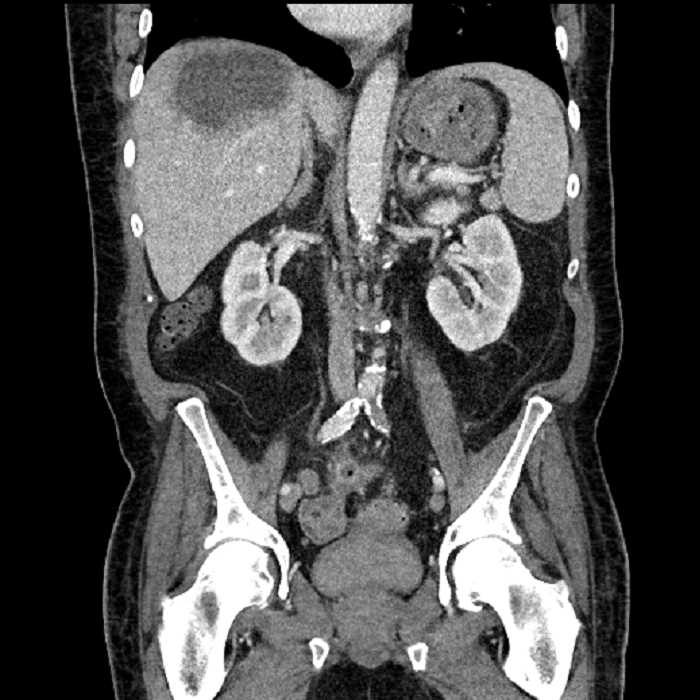

• Large fluid density structure in hepatic segments 7 and 8 measuring 10 x 7 x 7 cm with internal septation and circumferential ill-defined low density compatible with edema

• Clearly marginated fluid density structure in segment 7 and several other scattered tiny hypodensities, which likely represent cysts

• Mild mural thickening of a segment of the sigmoid colon with adjacent fat stranding and a 1.5 cm fluid and gas collection along the tip of an inflamed diverticulum

• Loss of the normal fat plane between this collection and adjacent loops of small bowel, which demonstrate mural thickening

• Hepatic abscess

Acute sigmoid diverticulitis complicated by a small contained perforation and a large abscess in the right hepatic lobe. Additional small subcapsular abscesses along the anterior margin of the left hepatic lobe.

Additionally, loss of the normal fat plane between the peridiverticular collection and adjacent thickened loops of small bowel raises the potential for an enterocolonic fistula.